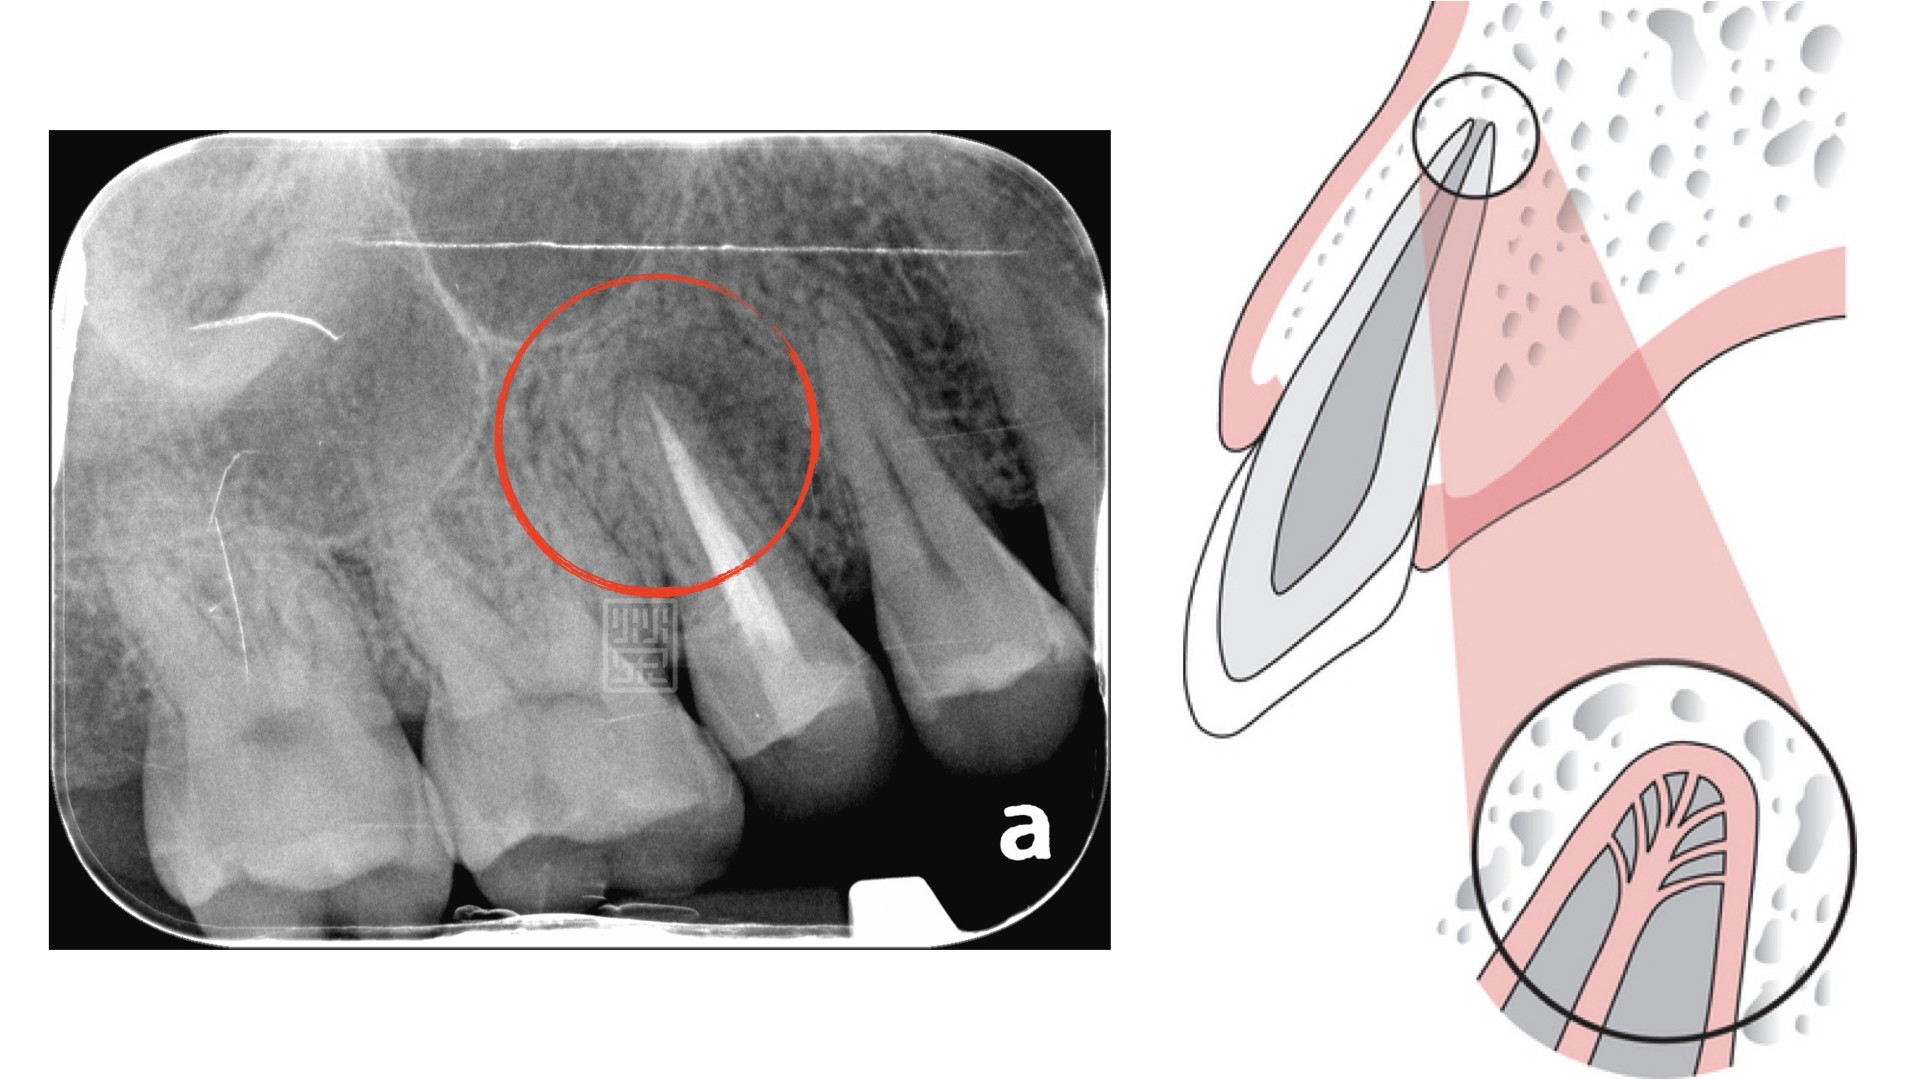

大笑後的尷尬---黑色銀粉填補

首先了解每位病友心中對美的要求,量身打造專屬牙齒美白治療方式,藉由牙周、根管、矯正、植牙、冷光美白、貼片、全瓷冠與顯微鏡微創治療,達到不只健康,更希望讓您發出打從心底燦爛自信的笑容。